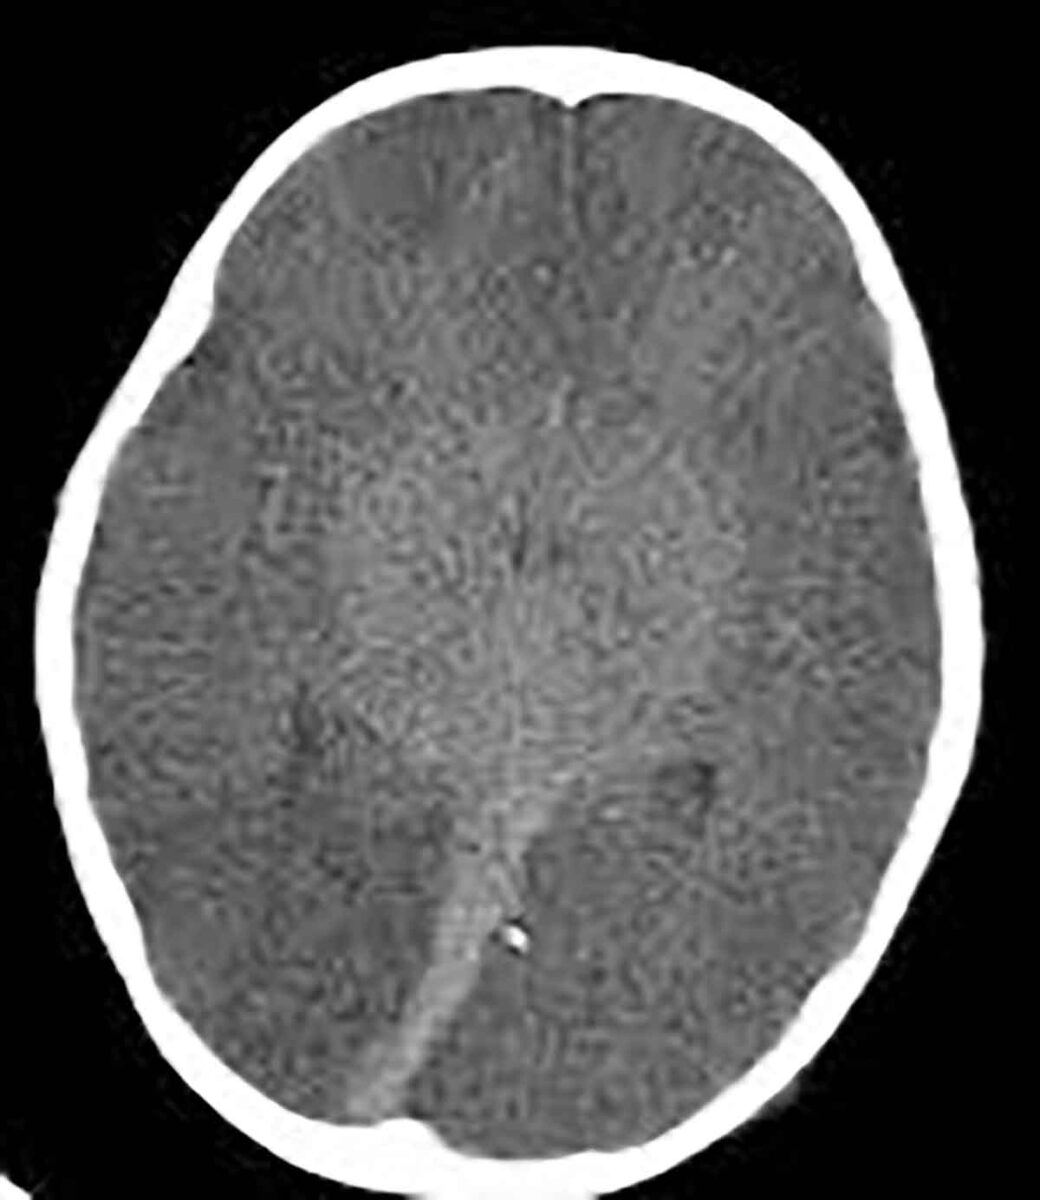

3. Exame complementar obrigatório, como eletroencefalograma (que identifica atividade elétrica cerebral), Doppler transcraniano (que avalia fluxo sanguíneo cerebral), cintilografia ou arteriografia cerebral. Todos têm como objetivo comprovar, por vias técnicas, que não há mais funcionamento cerebral.

Esses exames devem ser realizados com intervalo mínimo de tempo entre as avaliações, respeitando a idade do paciente e as normas da resolução. Só após a conclusão de todas essas etapas é emitido o Termo de Declaração de Morte Encefálica, documento legal que atesta o óbito.